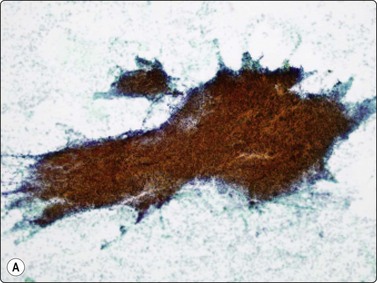

Other neoplasms

The most common sarcomas of this site include malignant fibrous histiocytoma and liposarcoma.131,132 Synovial sarcoma is well described.133 We have seen a single case of monophasic synovial sarcoma of mediastinum diagnosed on transoesophageal EUS FNB by the demonstration of SYT-SSX fusion transcripts by FISH on cell blocks, indicating X:18 translocation (all material shown here is courtesy of Dr. Anita Soma, PathWest QE II AP). (Fig. 9.10) The patient was a 45-year-old male with an 11-cm mass adjacent to the lower oesophagus, displacing the heart. Smears showed a rather bland spindle cell population but with mitotic activity. The cell block immunohistochemistry was negative for cytokeratins, CD117 and smooth muscle markers, making leiomyosarcoma and GIST unlikely. The tumor did show positive staining for CD99, BCL2 and CD34, raising the possibility of solitary fibrous tumor or synovial sarcoma. An SYT-SSX1 fusion transcript was detected by reverse transcriptase PCR, reinforcing the FISH cytogenetics. No other diagnostic procedures were undertaken (Fig 9.10).

image image image image image image image

Fig. 9.10 Synovial sarcoma

(A) Large infiltrative mass posterior to heart (Thoracic CT); (B) Loose fascicle of spindle cells including small blood vessels. Background of bare tumor nuclei (H&E, LP); (C) Loose cluster of bland spindle cells but with mitotic activity (H&E, HP); (D) Cell block, small spindle tumor cells with non-specific features (H&E, HP);(E) FISH on cell block, breakapart probe for SYT showing positive disruption of red-green-yellow components (FISH, HP); (F) FISH on cell block, fusion probe for SSX2 (green) and SYT (red) probes showing positive fusion of green and red components. (FISH, HP); (G) FISH on cell block, fusion probe for SSX2 (green) and SYT (red) probes showing positive fusion of green and red components (FISH, HP).